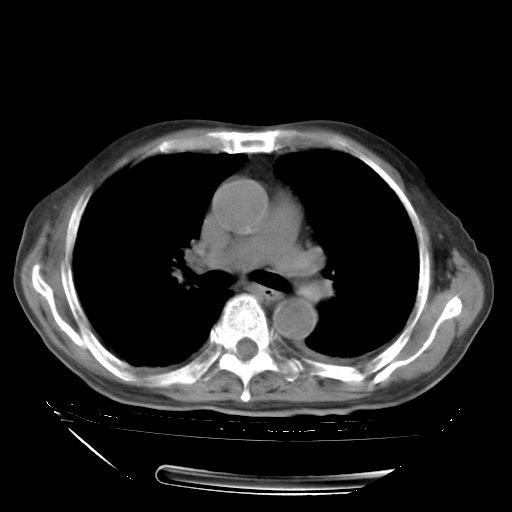

甲强龙80mg/日+抗结核治疗(异烟肼+利福霉素+乙胺丁醇)10天。复查肺部CT。

治疗10天肺部CT